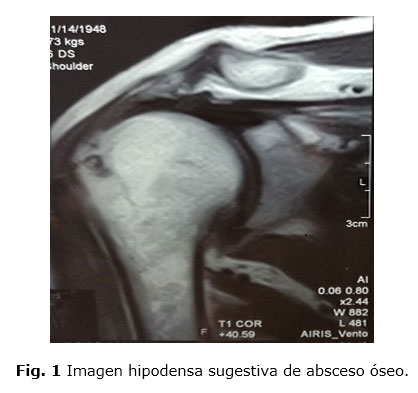

El resultado de la RMN aporta una imagen hipodensa, de 2,3 cm en cabeza humeral derecha, cerca del surco intertrocantérico, que puede ser compatible con la presencia de un AO (Figura 1). Con este diagnóstico se mantiene el tratamiento antibiótico y se realiza tres sesiones de aspiración del contenido e infiltración de 40 mg de acetato de prednisolona bajo supervisión y guía ecosonográfica. Además, se administró ozono (10 sesiones) por vía rectal y 4 sesiones intra articulares.

Los estudios imagenológicos fueron decisivos para establecer el diagnóstico definitivo de la enfermedad. En la radiografía simple de ambos hombros, en vista anteroposterior, se observó la presencia de una imagen hipodensa que sugería la presencia de un absceso óseo o una lesión tumoral a nivel de la cabeza humeral. Ante esta disyuntiva se realiza una RMN que es la que define los elementos radiológicos que posibilitan el diagnóstico del AO.